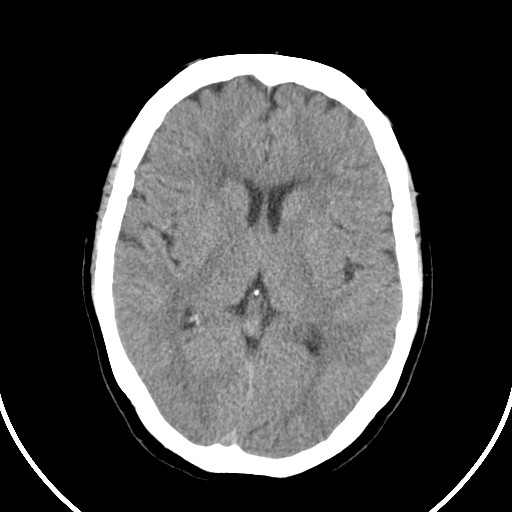

标题: CT21850:女,56岁,右中指淤肿,右手麻痹1天

女,56岁,右中指淤肿,右手麻痹1天

右侧基底节多发小梗塞

右枕叶低密度区伴硬膜下血肿——增强扫描或mri。

作者: huangyinshan    时间: 2009-8-25 15:37

右基底结区腔梗

右侧基底节区腔隙性脑梗塞

右侧基底节多发腔梗!

双侧侧脑室额角旁对称性略低密度影,边缘模糊,无占位效应,考虑轻度脑白质稀疏症(病人有高血压吗).,右枕叶低密度影多为伪影,不放心薄扫一下.

右枕叶条状低密度影不应该忽略可能极具意义